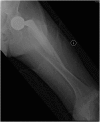

We report an 85-year-old patient with severe osteoporosis who had suffered from multiple episodes of periprosthetic fracture of the femur. Revision fixation with long-spanning cable plate for bisphosphonate-induced atypical periprosthetic femoral fracture was performed. Nonunion and implant failure occurred at 16 months requiring revision surgery using long-stem femoral prosthesis with cable-plate fixation. To further facilitate bone healing, allograft and bone morphogenetic protein (BMP) were added. Eventually bone union was achieved after one year.